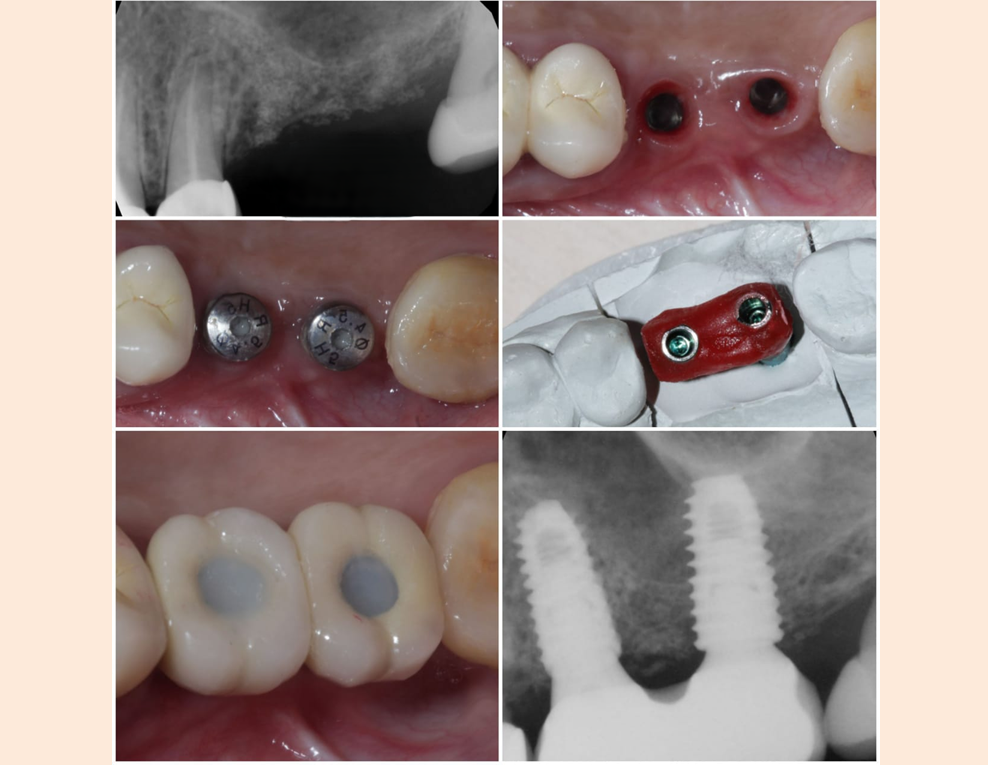

Most dental implants are secured in the jaw bone, providing a chewing surface almost as secure as that of natural teeth. Implants stimulate new bone growth in your jaw (osseointegration) locking the implant in place. Standardly for lower jaw, the implant is allowed to osseo – integrate and given crown after three months (approximately) and the upper jaw the implant is structured to crown or denture after five months as the upper jaw bone takes more time to osseointegrate. After the implant is osseointegrated, measurements are taken and the crown or denture is attached fixedly to the implant.

A standard dental implant has an Implant, a superstructure connected firmly to Implant – called an abutment, and the crown, which is to be fixed to the abutment. So, there are three firmly connected pieces in the dental implant for a tooth replacement. But there are also single piece implants.

Most of the time, implants can be placed immediately after tooth extraction if the extracted tooth is not highly infected [Immediate (placement) Implants]. And if the immediately placed implants are been stabilized better (primary stability), the implants can also be loaded with temporary crowns immediately (immediate loading). And later according to the gum level, after three to five months the implants can be loaded with permanent ceramic crowns.

Implant supported crowns-for single missing tooth